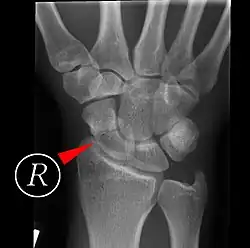

Scaphoid fracture before and after operation

Fractures of the scaphoid are the most common of the carpal bone injuries, because of its connections with the two rows of carpal bones.[1]: 177

Scaphoid fractures may be difficult to diagnose via plain x-ray. A repeat x-ray may be required at a later date, as might cross-sectional imaging via MRI or CT scan.[6]